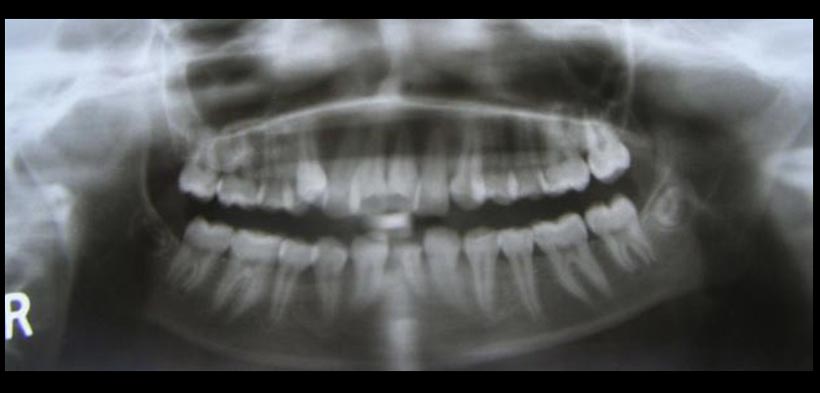

Fig. 2. La radiografía panorámica muestra la falta incisivos centrales inferiores y el incisivo lateral izquierdo.